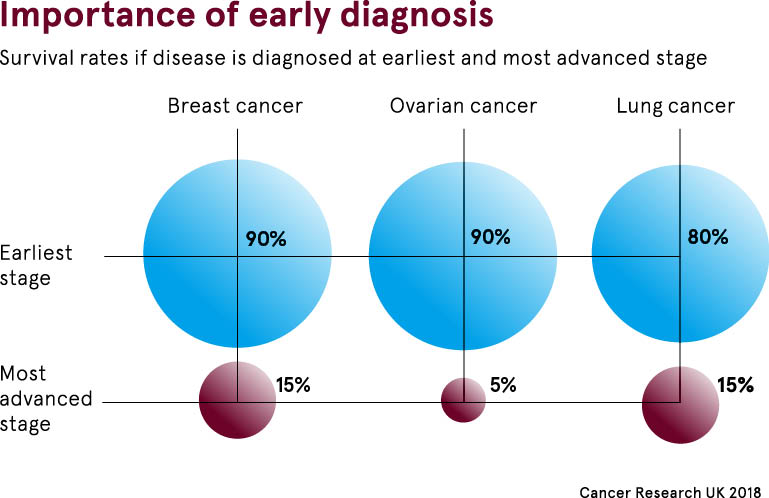

Data That Shows Early Detection Rather Than Late Detection In Breast Cancer